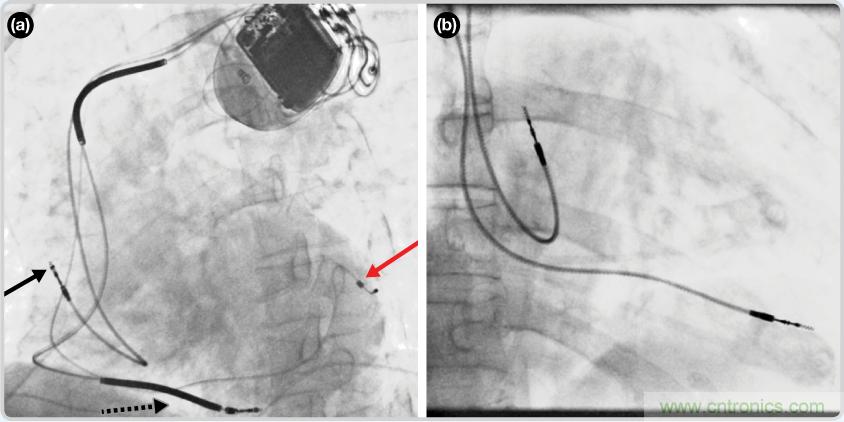

CRT器件在圖4(a)zhongdetoushituxiangzhongkeyikanjian。yishijiushiliyongzhezhongyingxianglaifangzhidaolianxiande。duiyufeizhuanyerenshilaishuo,zhezhongyingxiangshihennanjiedude。keyikandaoxinzangdandandelunkuo——zheshibodongzhongdexinzangdejingtaishitu。qiboqiweiyuyouxinfangshang,xinzangdingdianzhixiangyouxiafang。zaizhegedianxingdedaolianxianfangzhishilizhong,heisejiantouzhixiangyouxinfangdaolianxian。xuxianheisejiantouzhixiangyouxinshidaolianxian。hongsejiantoubiaoshidedaolianxianzhinengkandaoyibufen,zheshizuoxinshidaolianxian(紅箭頭指向電極尖端)。圖4(b)展示的是雙腔起搏器的典型導聯線放置透視圖像。右心房導聯線指向上方,置於右心房中。右心室導聯線則位於右心室頂部。

圖4. 起搏器導聯線放置的透視圖像3 (a). 單腔起搏器;(b).雙腔起搏器

3(a) http://en.wikipedia.org/wiki/File:Cardiac_resynchronisation_therapy.png.

(b) http://en.wikipedia.org/wiki/File:Fluoroscopy_pacemaker_leads_right_atrium_ventricle.png.